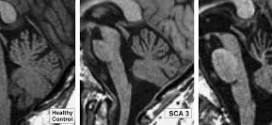

La Ataxia Espinocerebelosa (SCA3) se caracteriza por ataxia cerebelar progresiva. Como en todas las formas de ataxia, el primer síntoma normalmente es el deterioro de las capacidades para mantener el equilibrio, seguido después por incoordinación en las manos o dificultades en el habla (disartria). Algunos pacientes notan visión doble. Para el médico la apariencia de los ojos puede ser una …